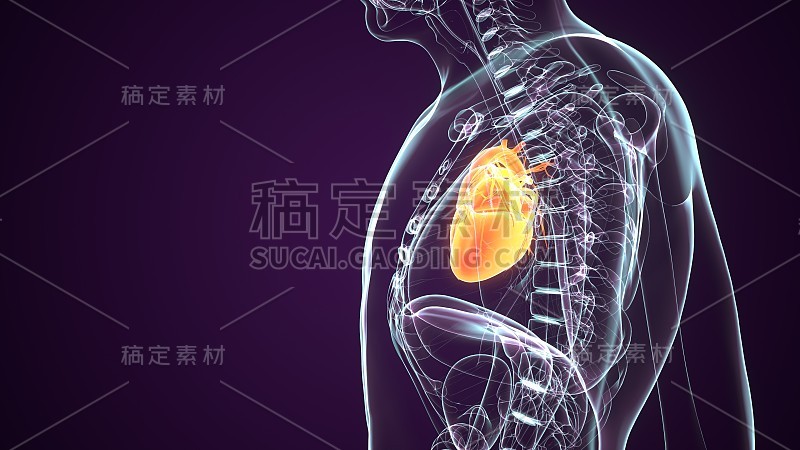

阿尼蒙冠状动脉详情